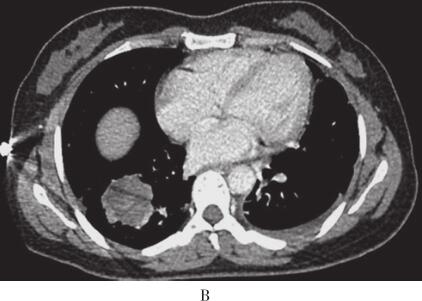

出院后定期随访,2013年7月患者出现间断左下胸痛,咳嗽时加重,余无不适。体检未见异常。复查胸部增强CT右下肺病灶较前稍增大,左下肺病灶较前减小(图2)。为排除恶性肿瘤,第3次行CT引导下经皮右肺肿块穿刺,病理检查示肺纤维化、玻璃样变及黏液变(机化),有少量炎性细胞浸润,未见肿瘤细胞。PAS染色及刚果红染色均阴性,确诊ELP。半年后患者胸痛症状有所好转,影像学同前,该病例在继续随访中。

图2 2013年7月3日肺部CT

与之前对比,右肺肿块较前稍增大,左下肺病灶较前减小